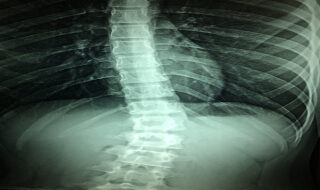

Transvaginal Mesh Victims: Undiagnosed Pudendal Neuralgia Improved with Spinal Cord Stimulators

Spinal cord stimulators have been a useful treatment for [...]